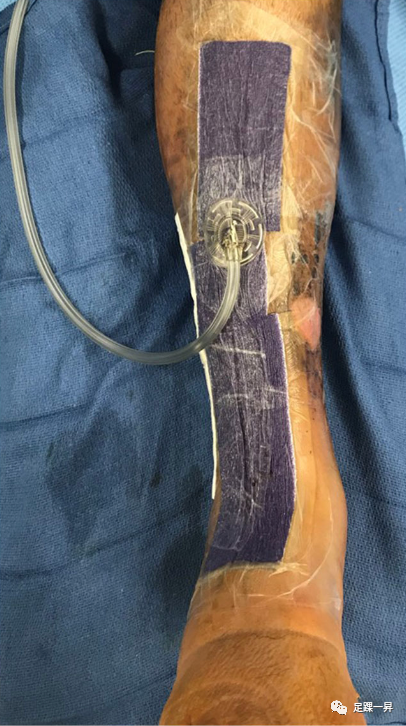

4. 开放性骨折

高能量胫骨pilon骨折可在12%至56%的患者中表现为开放性损伤,需要及时给予抗生素,必要时接种破伤风疫苗,并进行手术清创,最好在损伤后24小时内。神经血管检查至关重要; 对169例43 C型Pilon骨折的回顾性分析显示Gustilo-Anderson IIIA型和IIIB型骨折更常见于深部感染,尤其是当创伤伤口位于前方或内侧时。在无法完成创伤伤口一期闭合的病例中,可采用负压伤口治疗的临时方法来促进分期治疗。必要时,可采用负压伤口辅料治疗来覆盖伤口,减少水肿,并为闭合准备伤口床。放置抗生素Spacer或抗生素链珠是一个有用的辅助治疗开放性骨折骨缺损的手段。这些用于填充死腔,消毒局部环境,并产生用于移植的血管化包膜(例如,Masquelet技术)。

△图示术中照片提示高能开放性胫骨pilon骨折,前循环血供完全断裂。

△图示术中Gustilo-Anderson III型开放性pilon骨折,清创术后有严重的骨缺损。采用抗生素骨水泥填充,减少微生物感染,实现止血,改善机械结构,维持间隙,诱导生物膜用于延迟植骨。

△图示Pilon骨折术后采用负压伤口辅料来覆盖伤口。